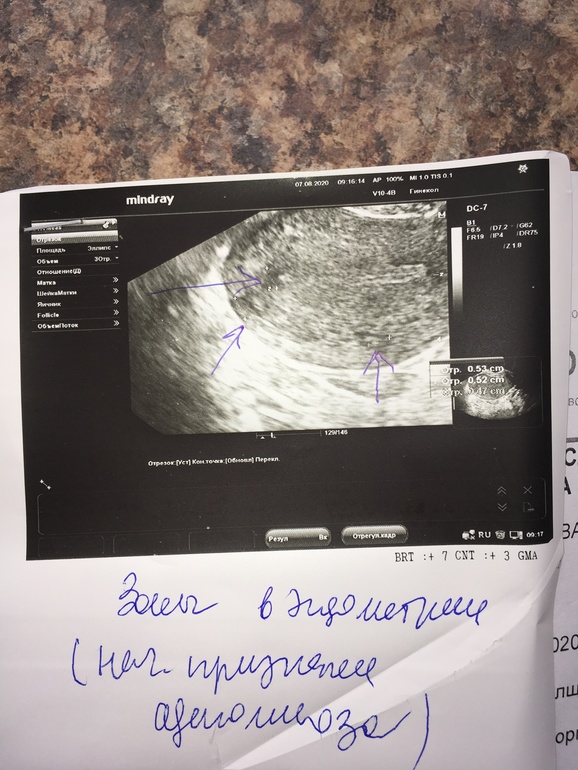

Сходила на узи , 6 дц - полипа нет 🤗кисты тоже 🤗 💃💃💃 но нашли какие-то очаги аденомиоза , такого ещё небыло 🤷♀️ Девочки , кто сталкивался ? Что за болячка такая? Мешает зачатию ? Как лечили? Приложу узи, чтоб сравнили , цикл у меня стабильный , но в этом цикле правда были болезненные месячные , но это учитывая кисту и то что было похоже на полип . Поделитесь , а то в интернете , чуть ли не рак написано.